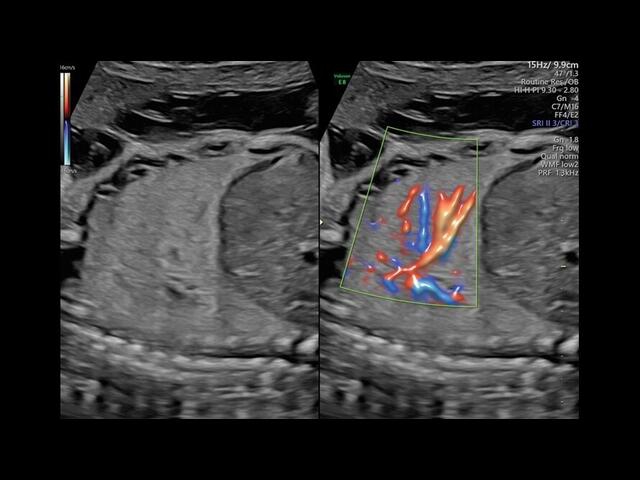

Система GE Voluson E8 обладает значительной вычислительной мощностью, которая позволяет решать даже самые сложные задачи в области диагностики плода. Она отличается высоким уровнем качества и статусом, предоставляя врачу потрясающие изображения во время 2D/3D-исследований. Кроме того, система всегда готова к использованию режима 4D благодаря чувствительному цветному доплеру.

Экспертное качество изображений достигается благодаря передовой технологии Speckle Reduction Imaging. Ее основное преимущество заключается в том, что она позволяет работать с высоким разрешением, сохраняя видимость исходной структуры ткани.

• HD-FlowTM для точного изучения кровотока и прорисовки сосудов.